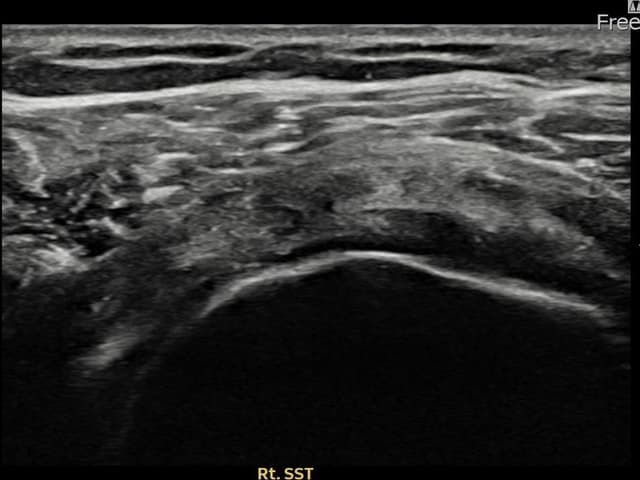

[経過期間: 23.09.01~23.11.03]

[縫縮術] 超音波検査にて右 棘上筋腱 滑液包面側部分断裂(8mm × 4mm (腱厚の約35%欠損))を確認。縫縮術施行後、腱の連続性が回復し、日常生活に復帰されました。